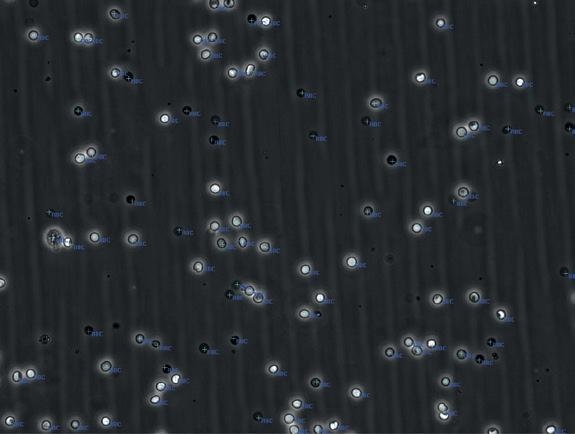

Researchers at the Carl R. Woese Institute for Genomic Biology (Urbana, IL, USA; igb.illinois.edu) have developed a new approach called LOCAPRAM that simplifies biomarker detection by removing the need for skilled professionals to analyze the resulting images. This development builds upon the team’s earlier work introducing Photonic Resonator Absorption Microscopy, or PRAM—a biosensing technique capable of identifying individual biomarker molecules, such as nucleic acids, antigens, and antibodies. In contrast to conventional methods, which measure signals from large groups of molecules, PRAM offers the sensitivity to detect and analyze single molecules.

PRAM images appear as a red field dotted with black specks. Though visually straightforward, determining which specks represent AuNP-tagged biomarker molecules requires expert analysis. To make this method suitable for point-of-care settings, the researchers proposed incorporating machine learning into the image analysis. Unlike other biosensing methods that primarily detect optical signals, PRAM produces microscope images, making it wellsuited for deep learning applications. To ensure high-quality data for algorithm training, the team imaged identical samples using both PRAM and scanning electron microscopy.

The AuNPs—nanoparticles roughly 1,000 times thinner than a strand of hair—appear as tiny black spots in PRAM images but are more distinctly

visible under electron microscopy. Through a labor-intensive process, the researchers meticulously cross-referenced every black spot seen in the PRAM images with the corresponding features in the electron microscope images to create an accurate training dataset for the machine learning model. This resulted in a deep learning-enhanced method known as Localization with Context Awareness, integrated with PRAM. This combined platform delivers precise, real-time molecular biomarker detection without requiring the intervention of a technical specialist. When evaluated, the findings published in Biosensors and Bioelectronics showed that LOCA-PRAM outperformed standard techniques by identifying lower concentrations of biomarkers and reducing the likelihood of false positives and negatives.

Image: A machine learning method is helping to bring diagnostic testing out of the lab (Photo courtesy of 123RF)